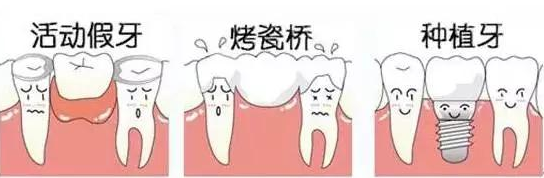

但是对于已经掉的牙齿,我们也不能任由它就一直这么缺失下去。随着现在人们对于牙齿口腔健康的愈加重视,牙齿缺失后修复的方法也有很多,目前使用比较多的是活动假牙、烤瓷牙、种植牙。

活动假牙想必大家都能理解,一般我们爷爷奶奶们会使用那种每天都需要摘下来的,吃饭一点都不方便的假牙,这种假牙比较便宜,但是相对的每天的清洁比较麻烦,而且吃东西都嚼不烂,对于年轻人来说,可能选择的还是比较少的吧。》》》推荐阅读:什么是种植牙,种植牙有风险吗?成功率是多少?

烤瓷牙和种植牙都是固定假牙,也是年轻人选择较多的牙齿修复方式。不过相对种植牙,烤瓷牙需要磨小两边的健康好牙然后做个搭桥式的修复,虽说是固定,但是没有自己独立的牙根,对于有些食物可能我们得说baybay了。

种植牙是目前修复缺失牙齿较佳的方式,也是争议较大的。它坚固,有独立的牙根,不需要磨损相邻的健康好牙;它耐用,种植后能使用很长的时间;它舒适,就像真牙一样的扎根在牙槽骨里,口腔没有异物感;它方便,只需要像正常牙齿一样的去清洁护理就可以;它美观,如果不是自己说,很少有人能发现那是做的种植牙。那么好的牙齿修复方式,伴随着它的是价格比较高等一些小情绪。但是想想我们的牙齿要用很多年的,如果每年这么折合下来的话,平均每天也就一块钱到几毛钱,现在几毛钱能做什么?买个馒头还得一块呢。